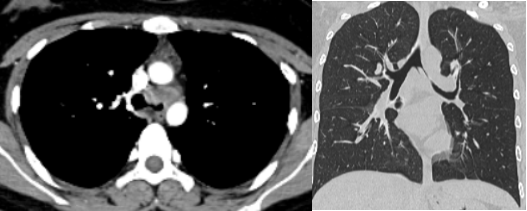

2023年11月,患者无明显诱因出现痰中带血,伴有明显的胸闷、胸痛症状,于2023年12月在外院完善了胸部CT、穿刺活检确诊为腺样囊性癌。肿瘤不仅侵袭了气管下段,致气管下段及左右主支气管壁增厚;还侵及隆突、右主气管上段及左主支气管全段,致左主支气管狭窄,左肺通气功能明显受限。

患者术后恢复良好,胸闷、胸痛等症状消失,且没有其他不适感。术后一个月,患者复查胸部CT提示重建气道通畅,吻合口愈合佳。患者目前已出院在家休养,随访了解到,患者已准备继续完成学业。